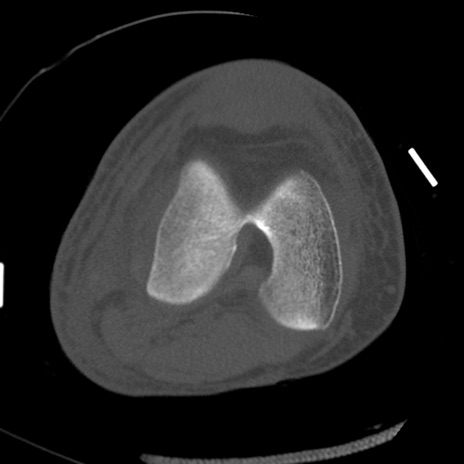

症例28 右膝関節CT(横断像)

右膝関節CT